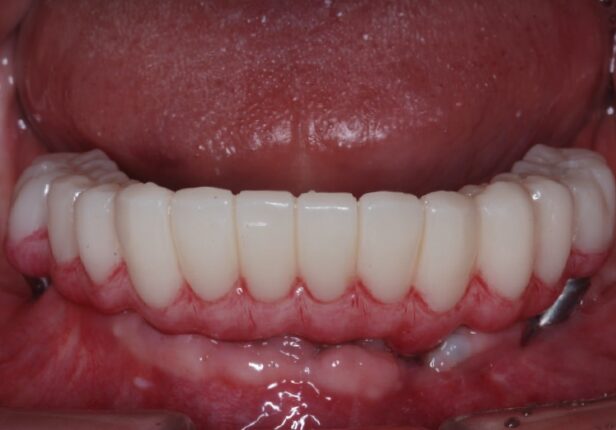

Mandibular Full case

Temporary Crown right after the placement (1st:: Shell)

Temporary Crown after 1 month (2nd)

Temporary Crown after 10 months